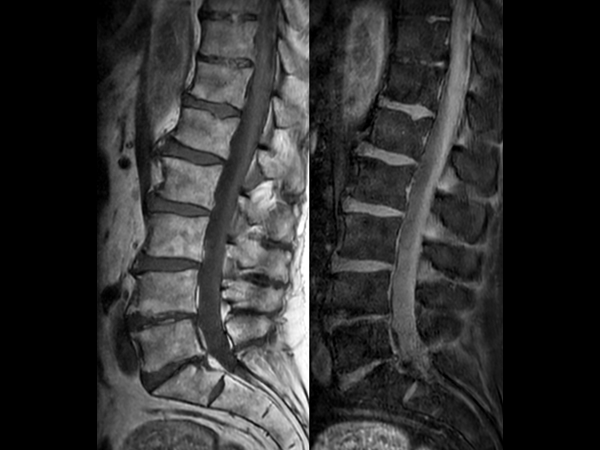

Comprehensive Lumbar Spine imaging at 3.0T